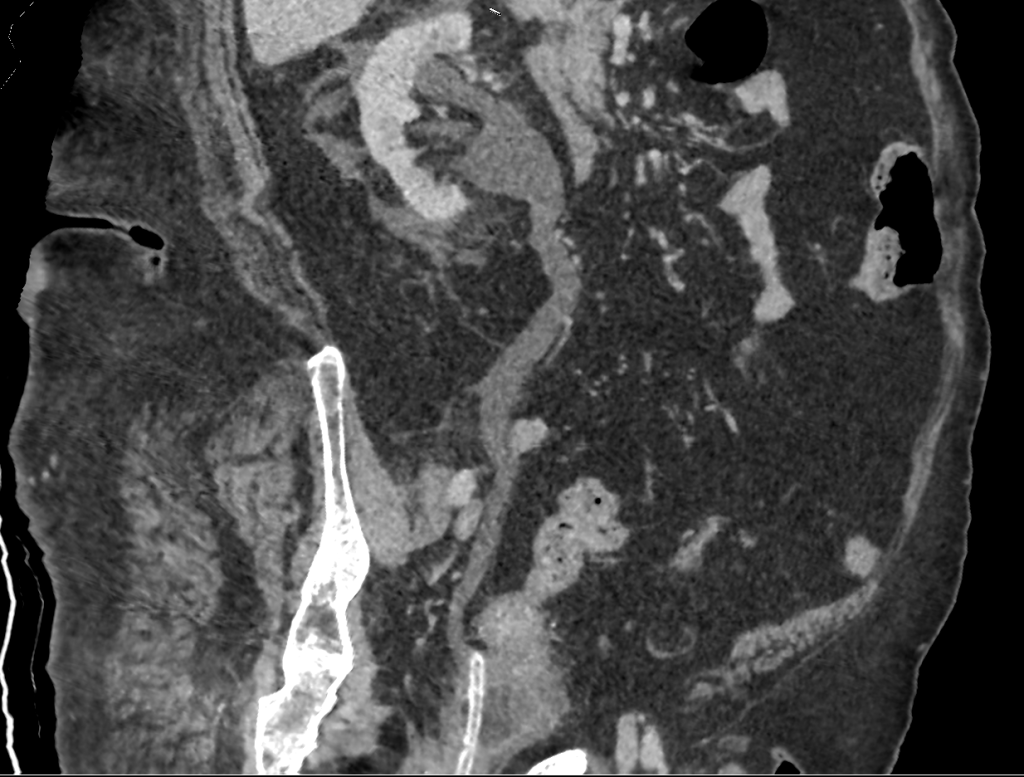

Een 68-jarige patiënte, bekend met recidiverende urineweginfecties bij een verblijfskatheter, wordt wegens koorts en pijn in de linkerflank opgenomen op verdenking van urosepsis. Zij wordt met antibiotica behandeld en de katheter wordt verwisseld. Na 5 dagen ontwikkelt zij plotseling hevige pijn in de rechterflank. Een CT-scan toont naast een hydronefrose nog een andere afwijking.

Wat is er aan de hand?